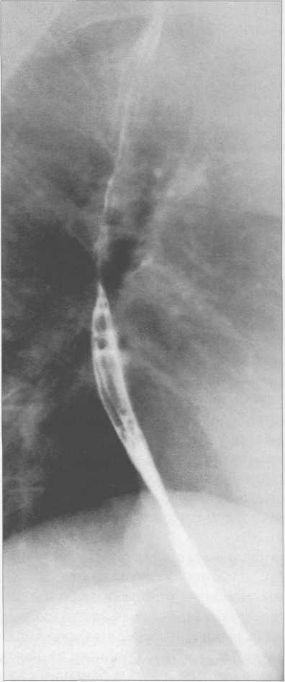

При контрастировании пищевод представляется в виде продольно расположенной лентовидной тени неравномерной ширины, расположенной в области шеи, в грудной и частично в брюшной полости (рис. 11.25—11.27).

Рис. 11.25. Рентгенограмма пищевода в прямой проекции.

1 —дуга аорты; 2 — смещение пищевода дугой аорты.

При контрастировании пищевод представляется в виде продольно расположенной лентовидной тени неравномерной ширины, расположенной в области шеи, в грудной и частично в брюшной полости (рис. 11.25--11.27).